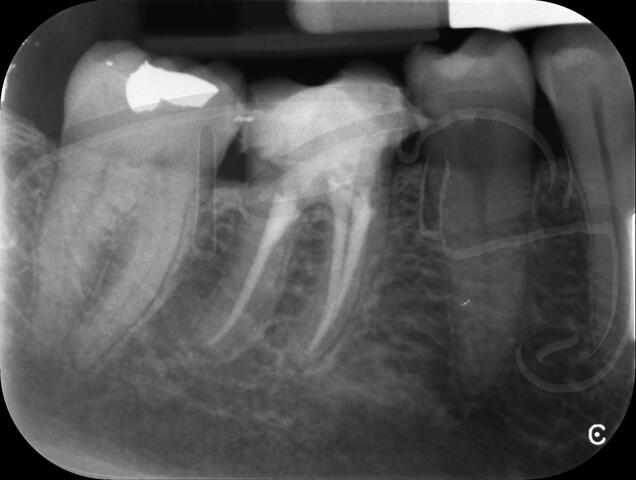

Endodontic Referrals

I am pleased to take endodontic referrals. Curved canals >30 degrees and potentially greater than 50 degrees can be negotiated. Sclerosed canals accessed. Post spaces prepared and the patient returned to you ready to restore.In most cases existing crowns, bridges and veneers can be retained with the endodontic access aesthetically restored after the full canal network has been treated.In the first instance I would prefer a radiograph and a brief list of patient expectations and a tooth history.

About: Root Canal Treatment

There are a number of ways to decide whether you need root canal treatment and the specific x-rays, scans and tests help diagnose your problem.An important sign is the type of pain you have been having with a tooth. It helps me decide if a tooth is in need of treatment and even if it saveable.

I really enjoy undertaking root canal treatments - rising to the challenge and helping people out of dental pain for the long term.I was privileged to be asked to speak at the 2016 BDA Conference, where I have a lecture about providing quality endodontic outcomes to patients, working as a generalist. Avoiding problems and pitfalls and maximising efficiency. One of the main matters that he covered was understanding that what is seen on plane radiography is utterly misleading and should not be the criteria by which a generalist continues treatment once it has been started.

At the 2016 BDA Conference, Thomas spoke about providing quality endodontic outcomes to patients, working as a generalist. Avoiding problems and pitfalls and maximising efficiency. One of the main matters that he covered was understanding that what is seen on plane radiography is utterly misleading and should not be the criteria by which a generalist continues treatment once it has been

started.